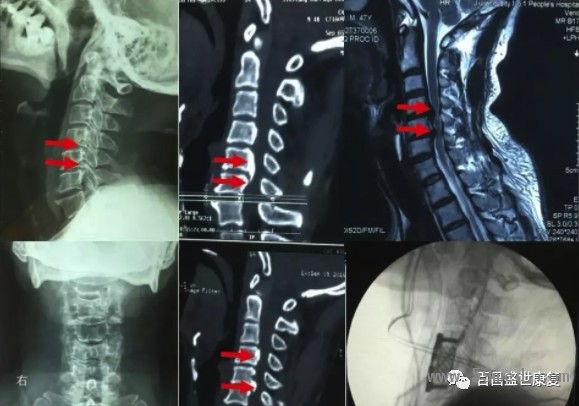

由于該型頸椎病起病隱匿,發(fā)作很緩慢,因此很多患者得不到及早診斷,就診時(shí)候已經(jīng)出現(xiàn)脊髓信號(hào)改變,從而導(dǎo)致不可逆性脊髓損傷。

因此對(duì)于此類型頸椎病患者,但凡有癥狀懷疑此型頸椎病時(shí),早期頸椎核磁共振檢查十分必要,若核磁共振提示脊髓壓迫導(dǎo)致脊髓信號(hào)改變,應(yīng)該盡快實(shí)施手術(shù)。

不同類型頸椎病表現(xiàn)不一樣,也有部分患者為混合上述分型中的一種或者多種類型,也叫混合型頸椎病。不同患者對(duì)疾病耐受程度不一樣,有些患者癥狀很嚴(yán)重,影像學(xué)檢查卻很輕;部分患者癥狀很輕微,影像學(xué)檢查已經(jīng)出現(xiàn)很嚴(yán)重的退變和脊髓神經(jīng)壓迫表現(xiàn)。

因此既不能單純根據(jù)癥狀判斷疾病的嚴(yán)重程度,也不能單純根據(jù)影像學(xué)病變確定治療方案。典型的臨床表現(xiàn),結(jié)合科學(xué)的影像學(xué)檢查綜合判斷,有助于確定頸椎病類型和疾病的嚴(yán)重程度,從而選擇合適治療方案。